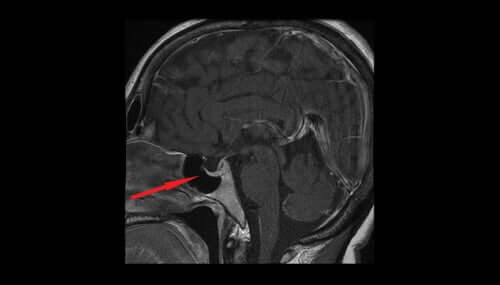

Argininvasopressin, även känt som antidiuretiskt hormon eller ADH, utsöndras från hypothalamus magnocellulära cellkärna. Därifrån överförs det till neurohypofysen och slutligen till blodsystemet. Det hjälper till att reglera vattenmängden i kroppen genom att kontrollera mängden vatten som njurarna utsöndrar. I denna artikel ska vi titta på egenskaperna och effekterna av hormonet argininvasopressin .

Låga nivåer av det antidiuretiska hormonet får njurarna att släppa ut vattenöverskottet. Detta gör att urinvolymen ökar, vilket i sin tur leder till uttorkning och en minskning av blodtrycket. Låga nivåer av antidiuretiskt hormon kan indikera skada på hypotalamus, hypofysen eller primär polydipsi.